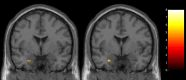

Findings: In addition to demonstrating feasibility, only BE-SMART-DR showed pre-treatment to post-treatment improvements in DR regularity (Cohen's d=0.55; 95% CI [0.06, 1.03]), associated with reductions in left amygdala responses to emotional face stimuli (p FWE (family-wise error)-SVC (small volume correction)<0.05), difficulties in emotion regulation (d=0.75; 95% CI [0.23, 1.25]) and suicide risk (d=0.65; 95% CI [0.15, 1.14]). Significant correlations were observed among these changes (p<0.05). Both interventions showed high acceptability and improvements in depression and mania symptoms. No intervention-related adverse events were observed.

Conclusions: Regularising DRs may enhance emotion regulation brain circuitry functioning, emotion regulation, and reduce suicide risk in BDAYA.